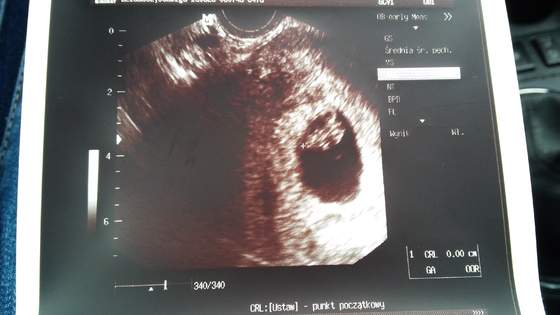

Byłam dzisiaj na usg i wszystko ok. 8 tydz i 2 dni.dzięki za kciuki :-D.

• 20150628_090021.jpg

20150628_090021.jpg

19,4 KB · Wyświetleń: 59

Betule zobacz na wątku z wizytami moją fotke też jest taki podłużny bo to zależy jak usg zrobi. W domu mam ocenę ciąży i ze 3 zdjęcia i na każdym pęcherzyk ma inny kształt więc się nie martw lekarz robił takie ujęcie żeby było wszystko dobrze widać:)